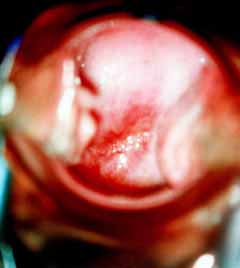

Κολποσκοπικές εικονες για τις αναγκες του forum.